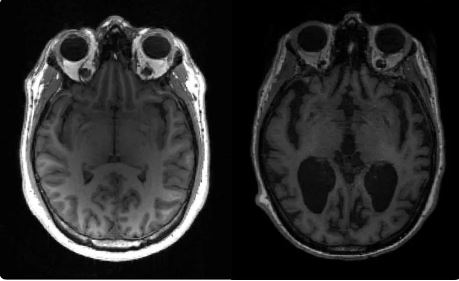

Alzheimer’s can now be detected with just one MRI scan

Alzheimer’s disease is the most common kind of dementia. It is diagnosed through a series of tests and scans. A single MRI scan can now detect the condition in 98 percent of cases. Doctors can diagnose Alzheimer’s disease with just one Magnetic Resonance Imaging (MRI) scan, according to research conducted by a team at Imperial … Read more